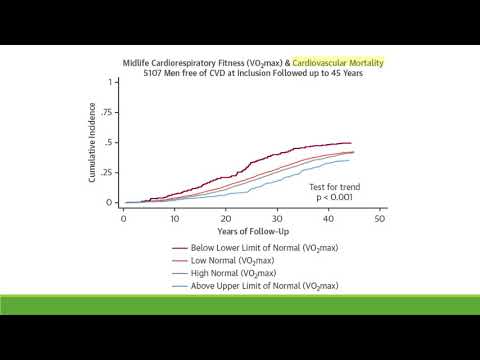

Entrenamiento cardiorespiratorio a mediana edad y la mortalidad a largo término. Dra. María Eugenia Doppler. Residencia de Cardiología. Hospital C. Argerich. Buenos Aires